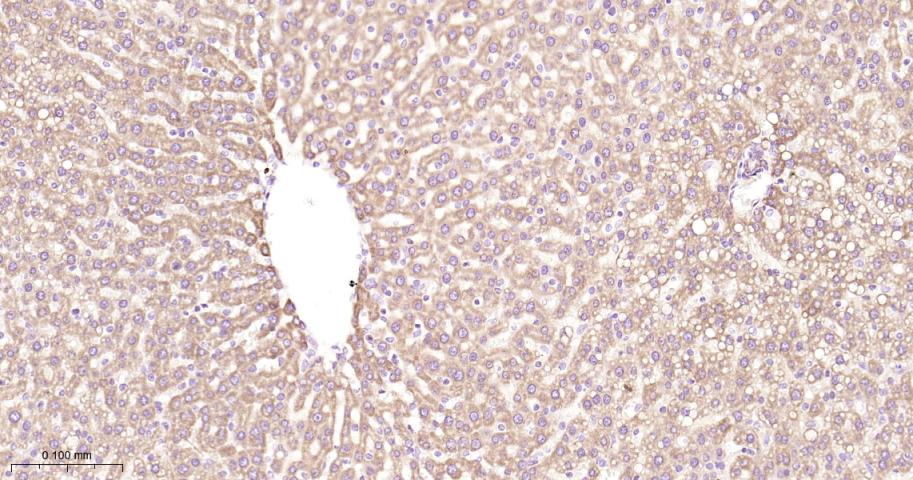

Paraformaldehyde-fixed, paraffin embedded Rat Liver; Antigen retrieval by boiling in sodium citrate buffer (pH6.0) for 15 min; Antibody incubation with PHB1 Monoclonal Antibody, Unconjugated(bsm-61208R) at 1:200 overnight at 4°C, followed by conjugation to the bs-0295G-HRP and DAB (C-0010) staining.